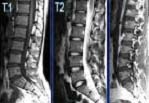

-Bệnh nhân có các biểu hiện nói trên sẽ được làm các xét nghiệm máu, dịch khớp, chụp X-quang cột sống, đặc biệt là khớp cùng chậu;

-Trên phim X-quang có thể phát hiện thấy các triệu chứng điển hình của bệnh như viêm khớp cùng chậu hai bên, hình ảnh cầu xương nối liền hai thân đốt sống do xơ hóa bao khớp, cột sống có hình ảnh thân cây tre do cầu xương nối liền nhiều thân đốt sống, dải xơ dây chằng cạnh cột sống trông như những đường ray tàu hỏa, đốt sống biến dạng thành hình vuông;

-Hiện nay, chẩn đoán sớm bệnh người ta có thể áp dụng phương pháp cộng hưởng từ hạt nhân (MRI), tìm yếu tố HLA B27, dương tính trong 90% bệnh nhân VCSDK trong khi đó chỉ có 4% dân số mang yếu tố này;